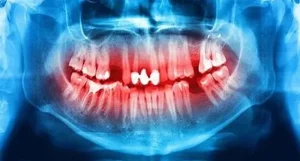

Tooth decay is one of the most common health problems worldwide, affecting individuals across all age groups and demographics. While cavities are often associated with

Tooth decay is one of the most common health problems worldwide, affecting billions of people across all age groups. While we often talk about “having